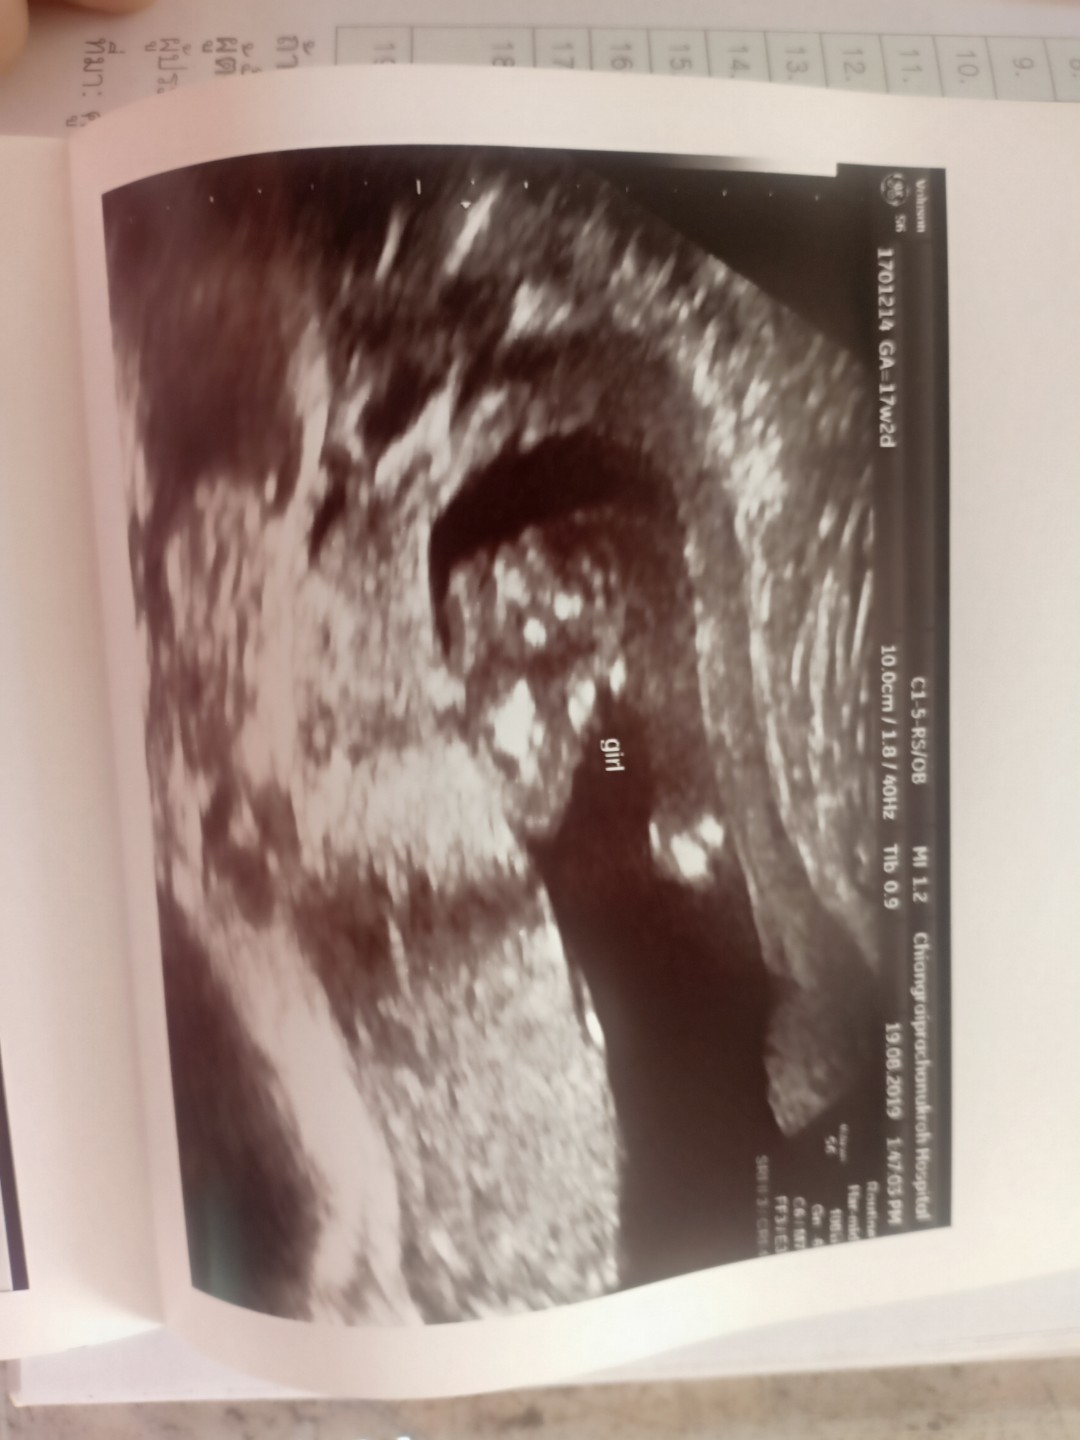

บ้านนี้มีกลีบค่ะ ชัดแจ๋ว😊😊

หมอบอกว่าหนูไม่มีจู๋คะ 😁😁😁

ท้องสองกลีบอีกแล้วววค่ะ😂😂